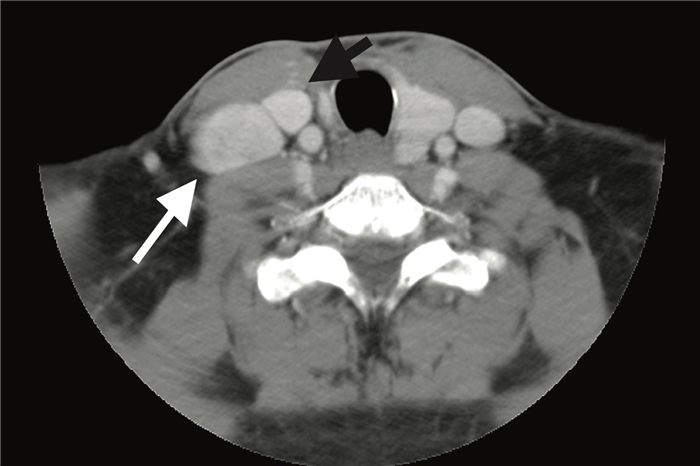

(Слева) КТ с КУ, аксиальная проекция. Патологическое образование поднижнечелюстного пространства, расположенное кпереди от лицевой вены. Такая локализация характерна для лимфоузлов уровня lb. Поднижнечелюстная слюнная железа лежит кзади от лицевой вены. Узлы, расположенные кзади от железы, относятся к уровню II.

(Справа) КТ с КУ, аксиальная проекция. Новообразование латеральной поверхности шеи слева, расположенное глубже от грудино-ключично-сосцевидной мышцы. Нечеткие контуры и разрушение границ между жировой клетчаткой и мышцей говорят о наличии экстракапсулярного распространения, четкого признака злокачественного процесса. (Слева) КТ с КУ, аксиальная проекция. Выраженное увеличение лимфоузла II уровня. Если судить только по размеру, лимфоузел является злокачественным; но его почкообразная форма говорит в пользу доброкачественности процесса (реактивный узел).

На ниже представленном КТ снимке визуализируется некроз лимфатических узлов группы IA.

На ниже представленном КТ снимке визуализируется лимфаденопатия группы IB справа.

На ниже представленном постконтрастном КТ снимке представлен пациент с карциномой языка и лимфаденопатией II группы лимфатических узлов.

На ниже представленном постконтрастном КТ изображении визуализируется увеличение и контрастное усиление лимфатических узлов III группы.

На постконтрастном изображении белой стрелкой указан увеличенный лимфатический узел IV группы. У пациента удалена правая доля щитовидной железы и правая яремная вена, что указано чёрной стрелкой, всвязи с папиллярной карциномой.